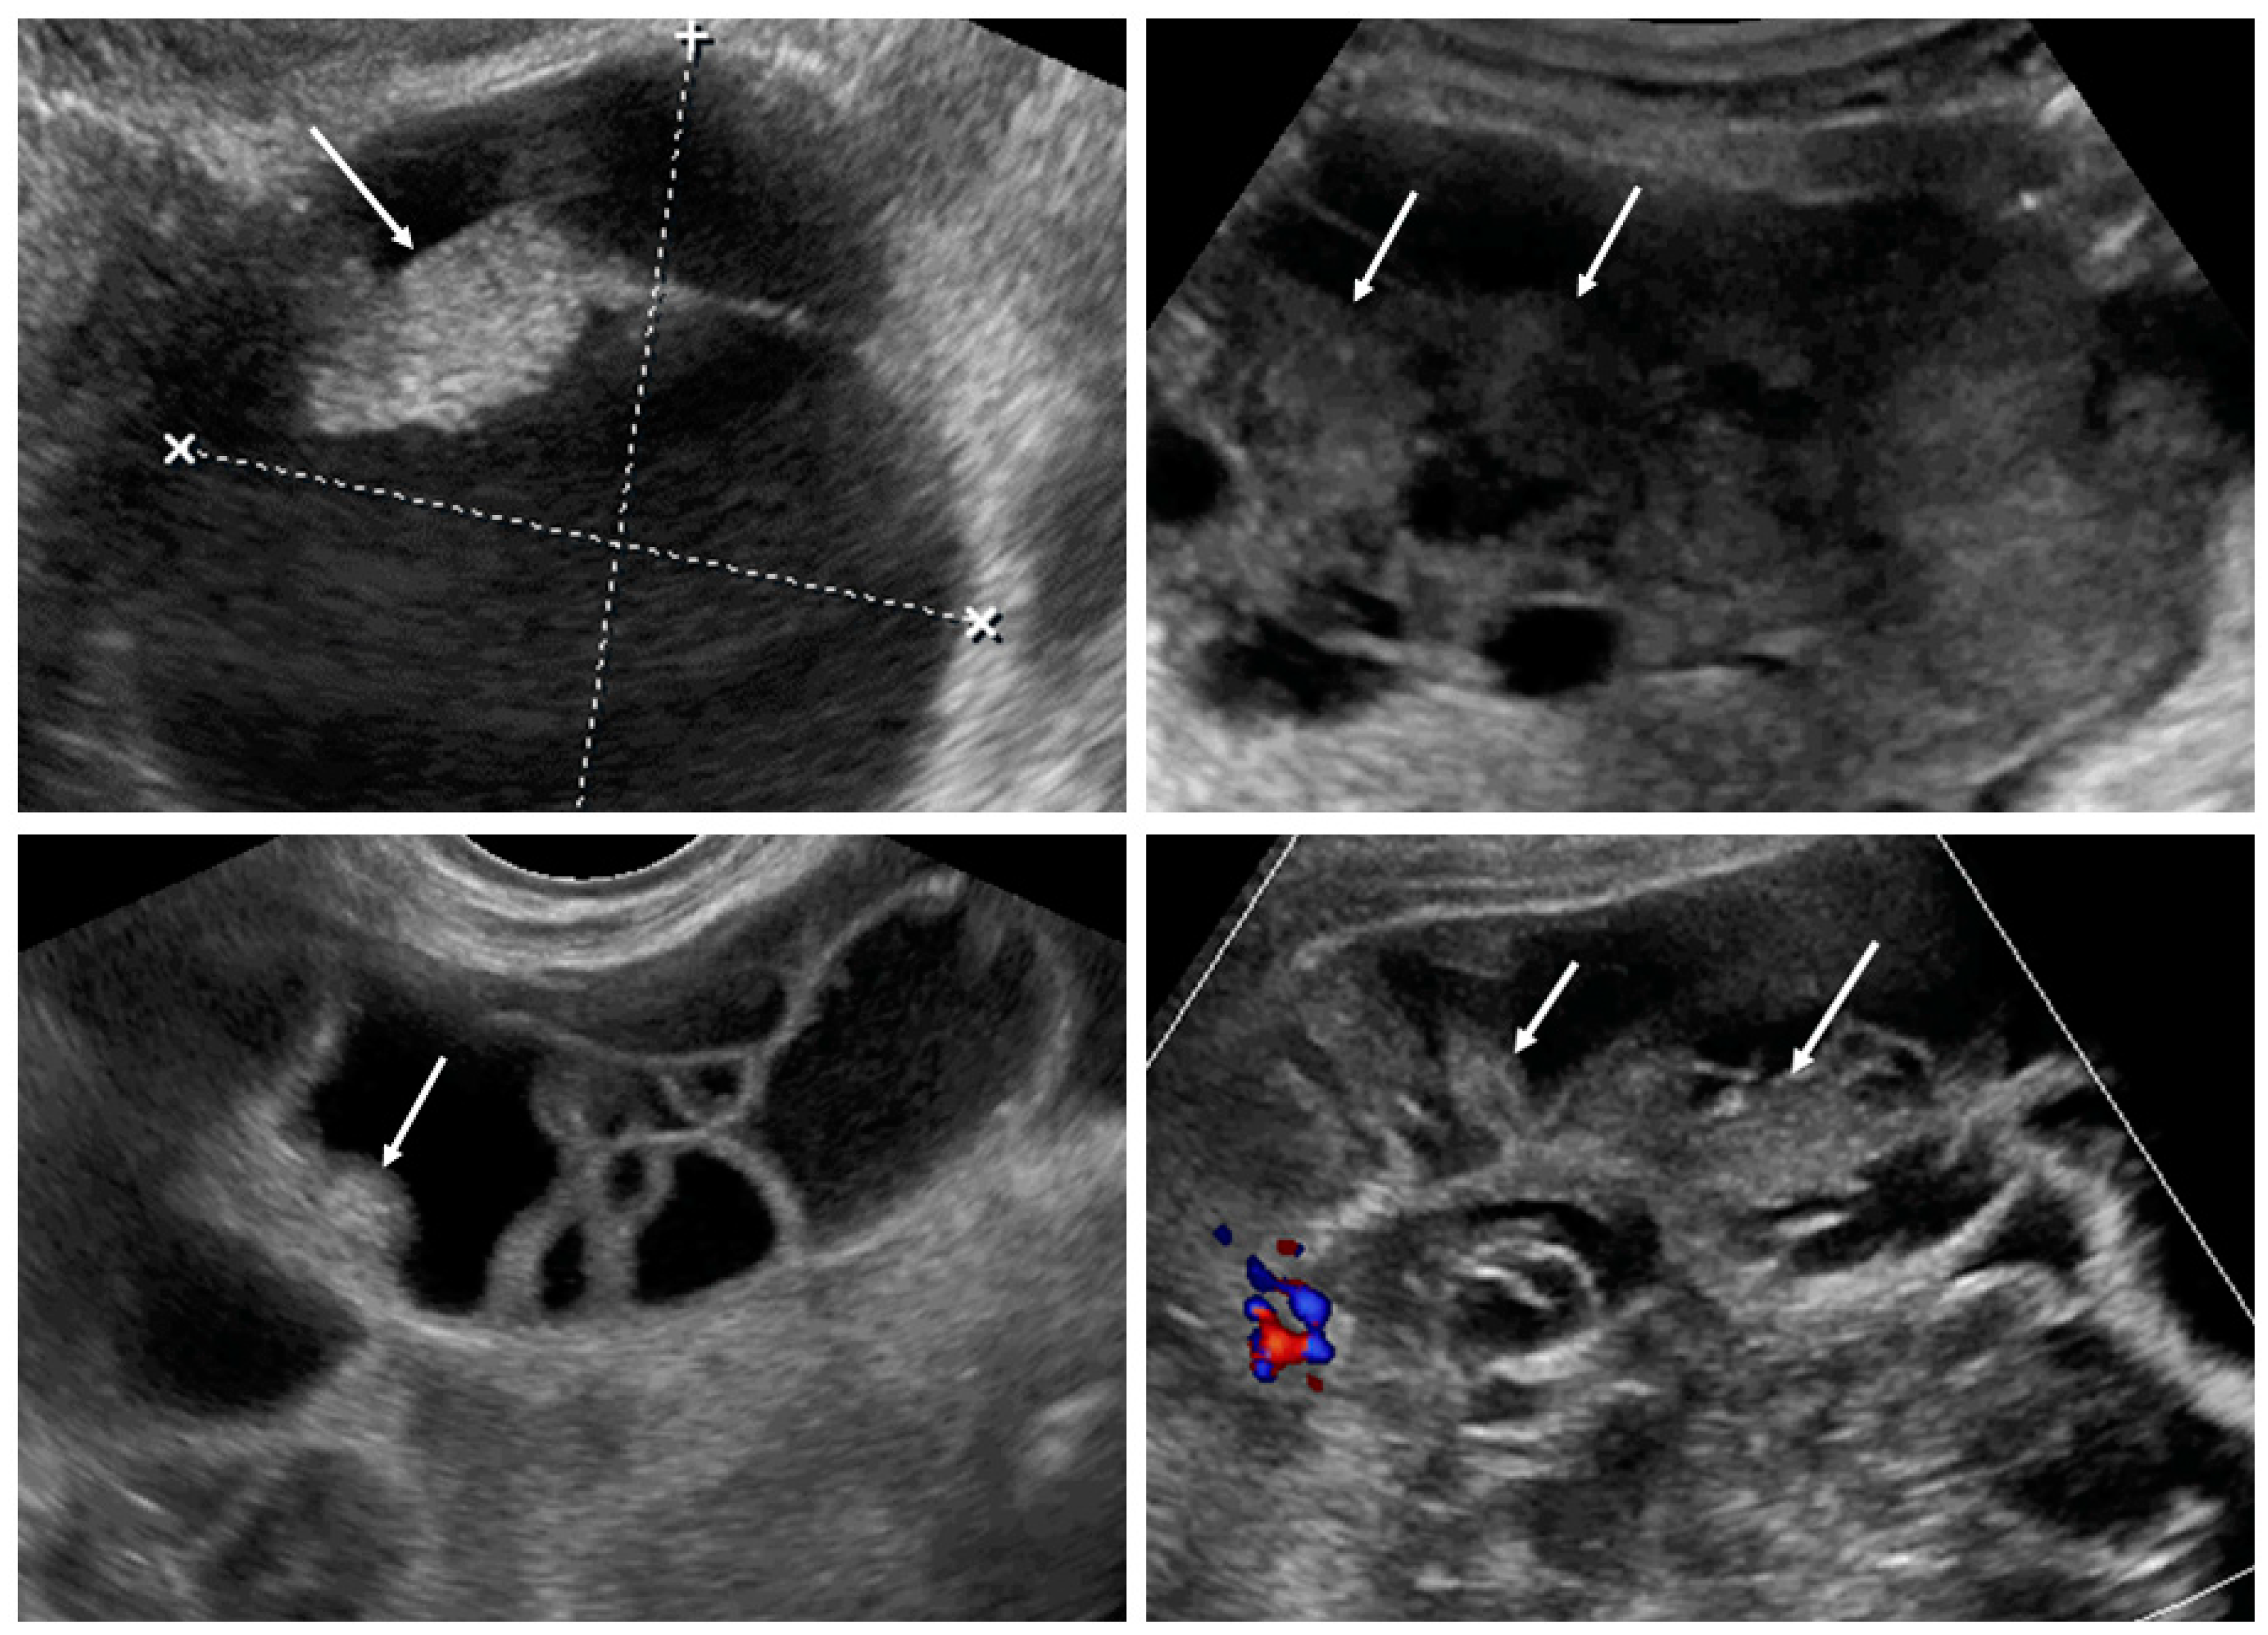

After the collection of cases for the study was closed, a new observation was noted (by M.S.) when analyzing the videoclips of ovarian mCRC in detail. A tree-like sign was detected in multilocular-solid tumors, with parallel, closely-localized, septa (“trunk”) later branching in different directions (“branches”), forming an image resembling a tree (Figure 5, Video S3). Interestingly, the tree-like sign was not detected in any of matched controls with primary OC.

Figure 5.

Tree-like sign in a multilocular-solid tumor. White arrows indicate the “tree trunk”; yellow arrows indicate “tree branches”.